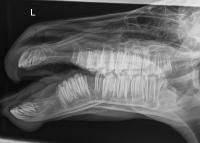

In its “Case of the Month,” the University of California, Davis (UC Davis) highlighted the case of a newborn foal, named Quincy, who presented with a broken jaw. Later X-rays showed that the foal had completely displaced fractures of both of her mandibles, which had left her unable to nurse, according to UC Davis.1

Once cleared for surgery, the team with the Diagnostic Imaging and Anesthesia Services performed a CT scan to classify the fracture and help guide surgical planning.

After the team talked to Johnson, it was decided that they would stabilize Quincy's fractures with external fixators. Her fractures were then reduced by Scott Katzman, DVM, DACVS-LA, associate professor and chief of service alongside Bridget Ratliff, DVM, with David Orozco-Lopez, DVM—both UC Davis surgery residents. Moreover, locking compression plates were placed on the exterior of Quincy’s face. Accurate fracture reduction and proper placement of the external implants were consequently confirmed with intraoperative fluoroscopy.

X-rays taken at 2 recheck visits confirmed that she was healing properly. Five weeks post-surgery, the fixators were removed. The injury occurred in late February, and Johnson has since reported that Quincy’s recovery is complete.1